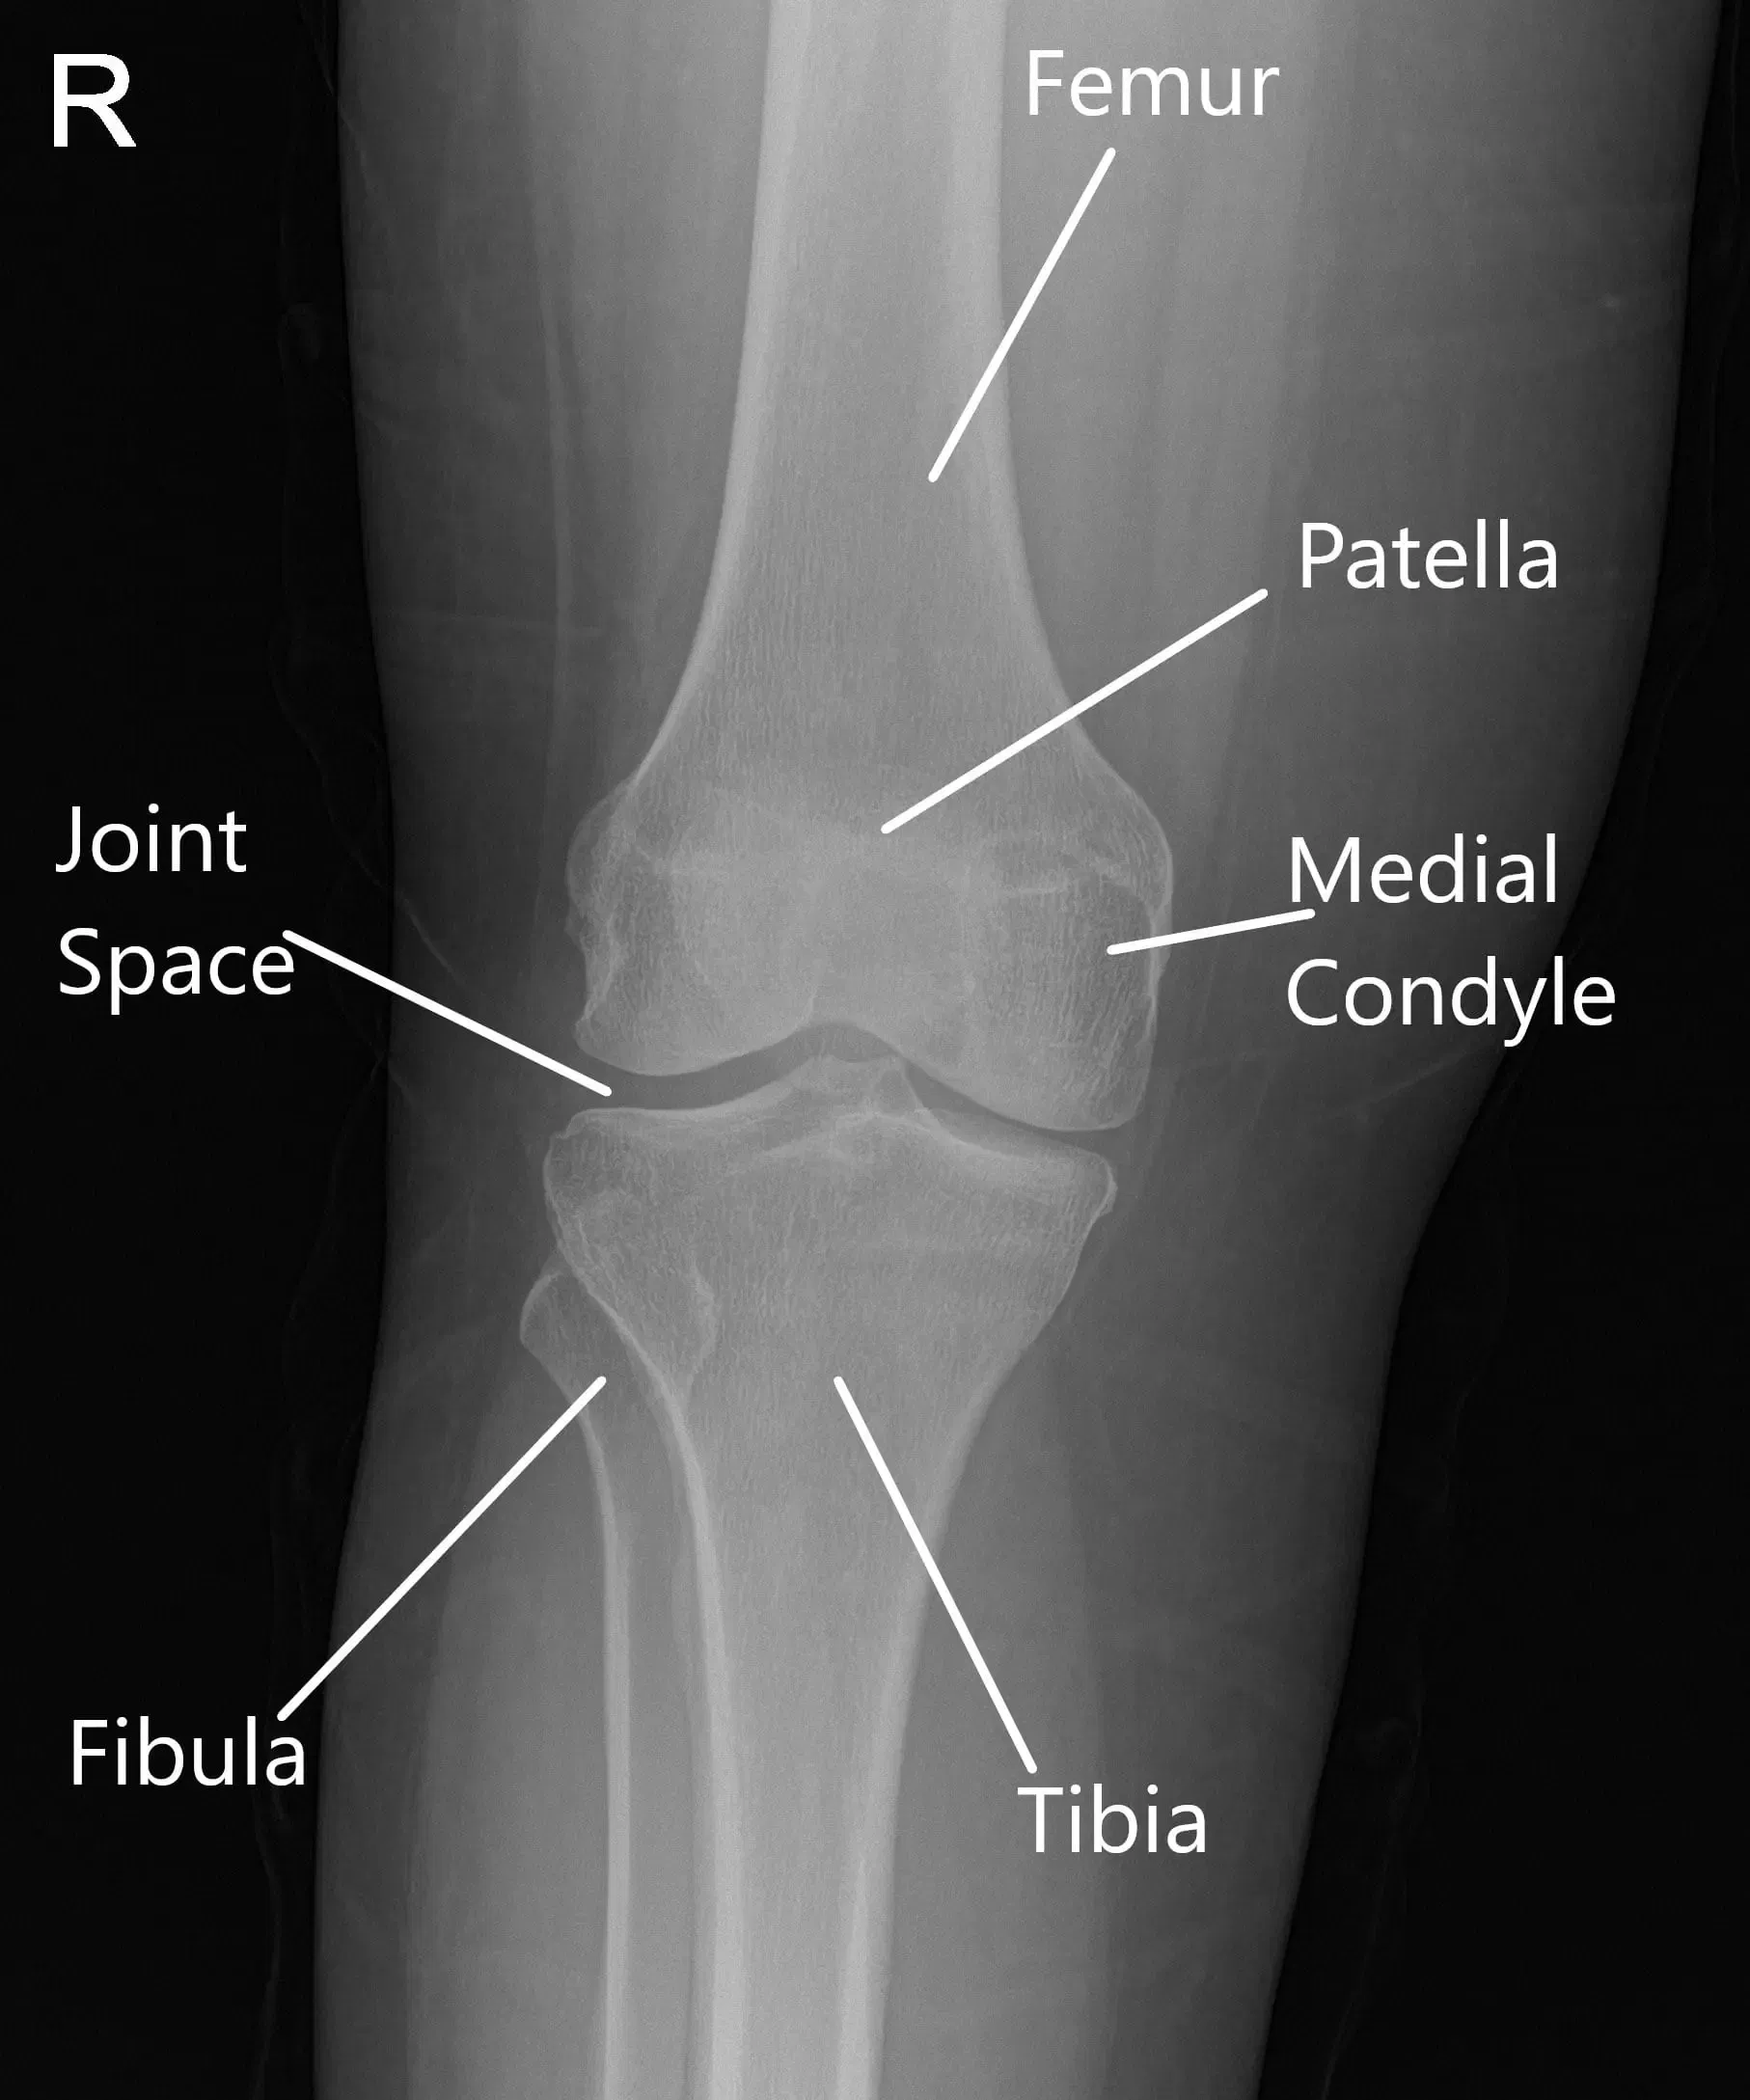

X-Ray of the right knee suggested mild osteoarthrosis in the medial and anterior compartment of the knee.